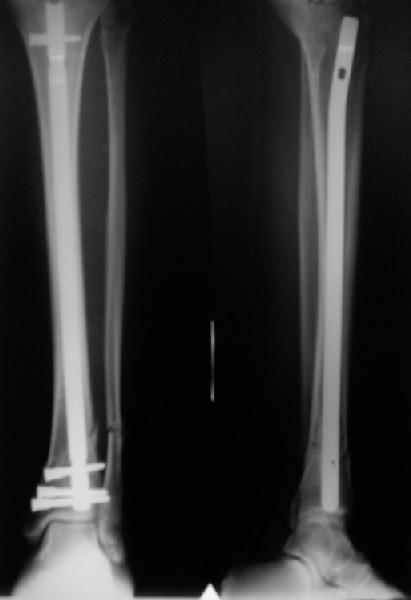

A typical case is attached, also an image with intra-op reduction obtained by a small wire distractor, in the moment of insertion a Poller wire in AP direction. Fixation by a SIGN nail. Despite the fibula was not fixed healing was obtained with the unchanged alignment.

In delayed cases acute length restoration performed only in the tibia may leave the fibula shortened thus change the mortise. So it is reasonable to restore length of both bones simultaneously by distractor and fix the fibula not with open reduction and plating but just by a single perQ screw. Example attached.